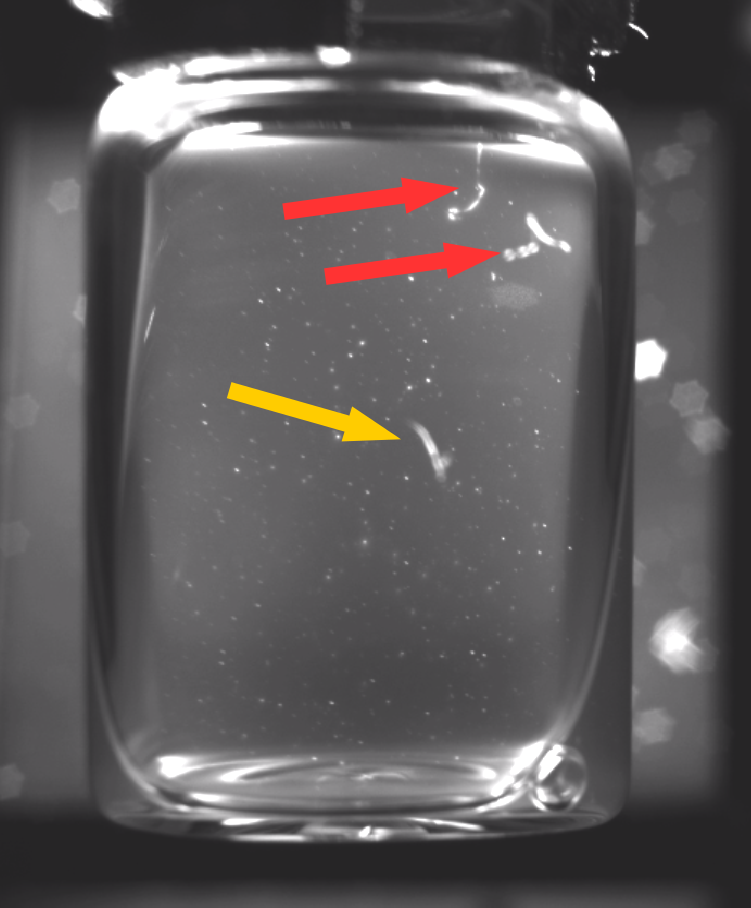

1) We outline our process for constructing a video dataset using vaccines supplied by the HAL Allergy Group. We built an automated vial rotator (AVR) for inducing the moving contrast necessary to identify anomalies [20]. However, recordings suffer from motion blur over the first 20 – 40 frames due to particles moving at a high velocity after the vial is spun (See Fig. 3). Due to motion blur good particles within the vials can appear elongated, making them hard to distinguish from anomalies. To evaluate the extent to which motion blur affects classification accuracy we split recorded samples into segments consisting of 20 frames. We hand-labelled the segments based on the presence of anomalies, enabling us to construct a dataset of 14k training and 6k evaluation samples, derived from 160 vials.

Motion Blur: One of the challenges regarding tuning the camera prior to recording the vials, was to find a depth of field that provides a sharp focus for all the particles within the suspensions. This means that the aperture size has to be narrowed to enable a sufficiently deep depth of field. A smaller aperture requires longer shutter speeds in order for sufficient light to reach the camera’s sensor. Despite increasing the light emitted by our strobe to the maximum setting, we are only able to record using 25 fps, and as a result the initial 20 – 40 frames from each recording suffer from motion blur (Examples are provided in Figure 3). Therefore, due to particles’ increased velocity after the vial is rotated using the motor, even good particles appear elongated during the initial frames of each recording.